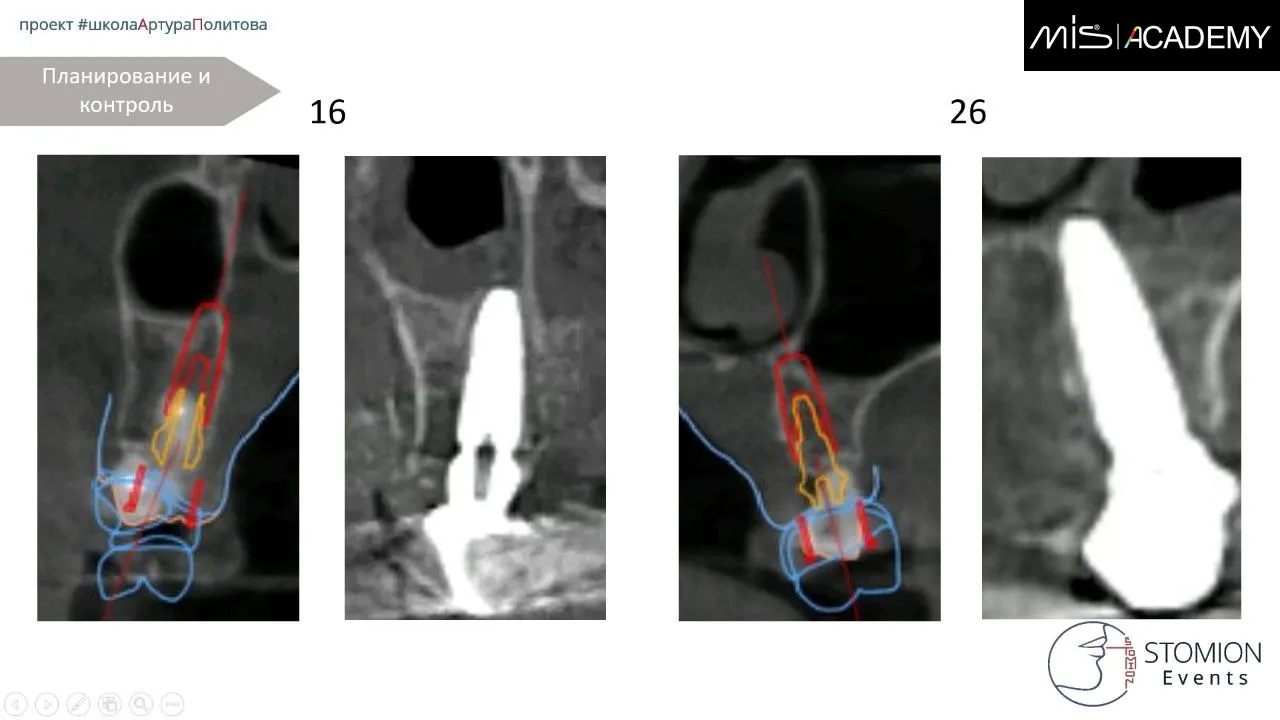

— Установка имплантатов MiS C1 в позициях 6-4-2-1-4-6.

— 1.6, 1.4, 2.4 — угловые МЮ,

— 1.2, 2.1 — коннекты,

— 2.6 — прямой МЮ.

При установке получилась вестибулопозиция имплантата 1.2, уже не помню причину, думаю смещение за счёт нёбной стенки, помню, что принято решение не менять позицию, конструкция будет под винт изибэйс для винтовой фиксации.